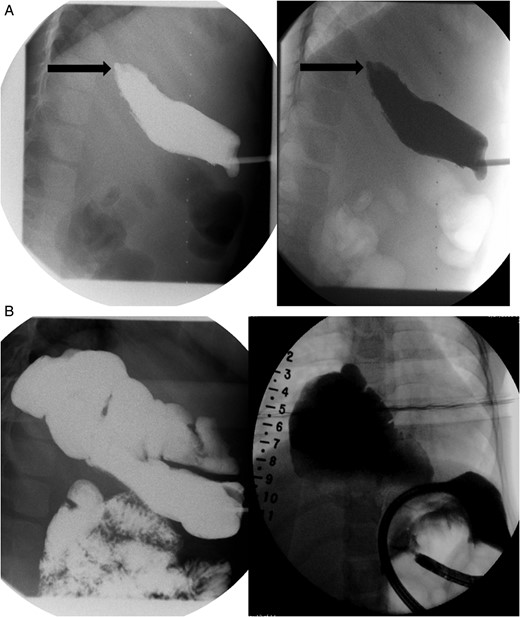

A fundoplication was performed during a subsequent hospital stay (postoperative day 237) for reflux. There was also concern for metaplasia of her distal esophagus from stratified squamous epithelium to simple columnar epithelium with goblet cells consistent with Barrett's esophagus. Her total follow-up to date has been 1377 days with her last endoscopy was performed on postoperative day 1159 from Stage 1 of her Foker procedure (Fig. 4).

Her last follow-up EGD demonstrating a patent native esophagus.